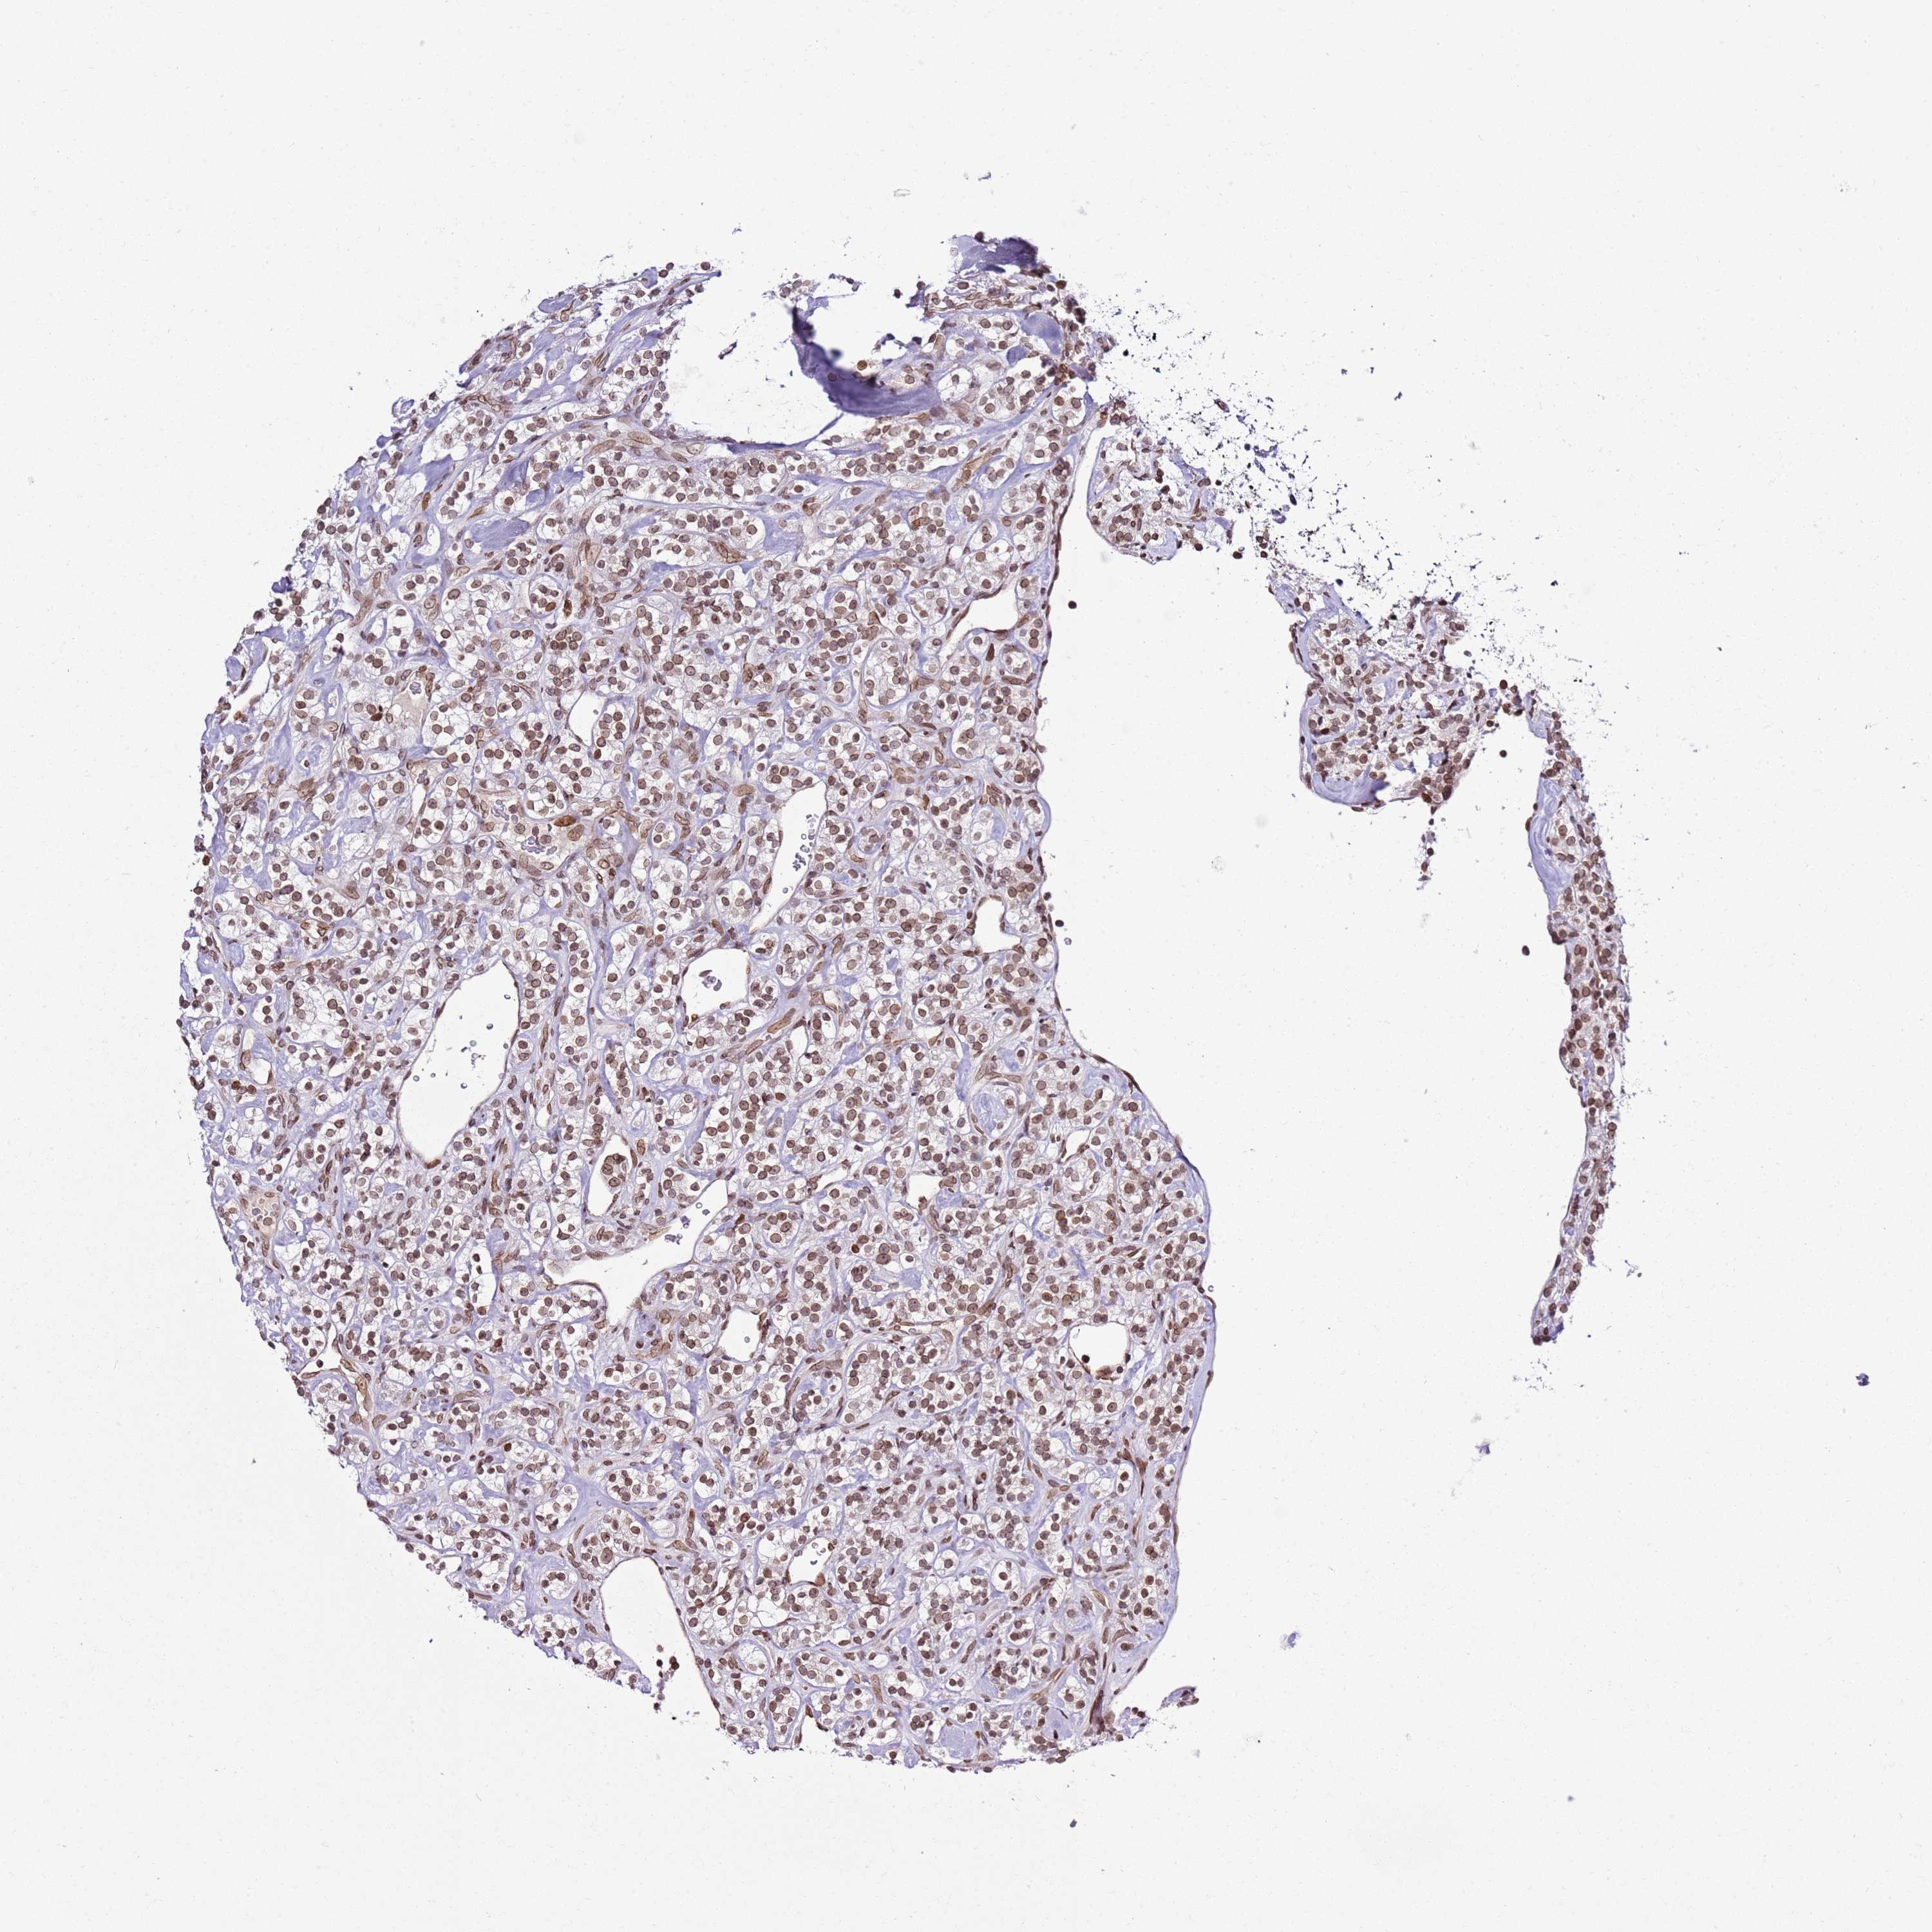

CANCER RENAL CANCER Show tissue menu

KICH TCGA KIRC TCGA KIRC VALIDATION KIRP TCGA PROTEIN RCC CPTAC PROTEIN EXPRESSION

KIDNEY RENAL PAPILLARY CELL CARCINOMA (TCGA) - Interactive survival scatter ploti

POU6F1 is not prognostic in Kidney Renal Papillary Cell Carcinoma (TCGA)